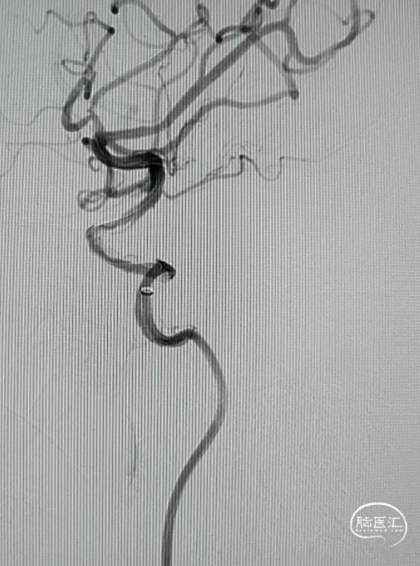

DCwire®微导丝通过闭塞段

微导管到达闭塞段以远真腔

释放4.0*30mm Syphonet®取栓支架

2.5*15mm SacSpeed®球囊扩张导管在C5段进行球囊扩张

2.5*15mm SacSpeed®球囊扩张导管在C1段进行球囊扩张

清理管腔血栓

回收4.0*30mm Syphonet®取栓支架

置入4.0*20mm 颅内支架

术后成形良好